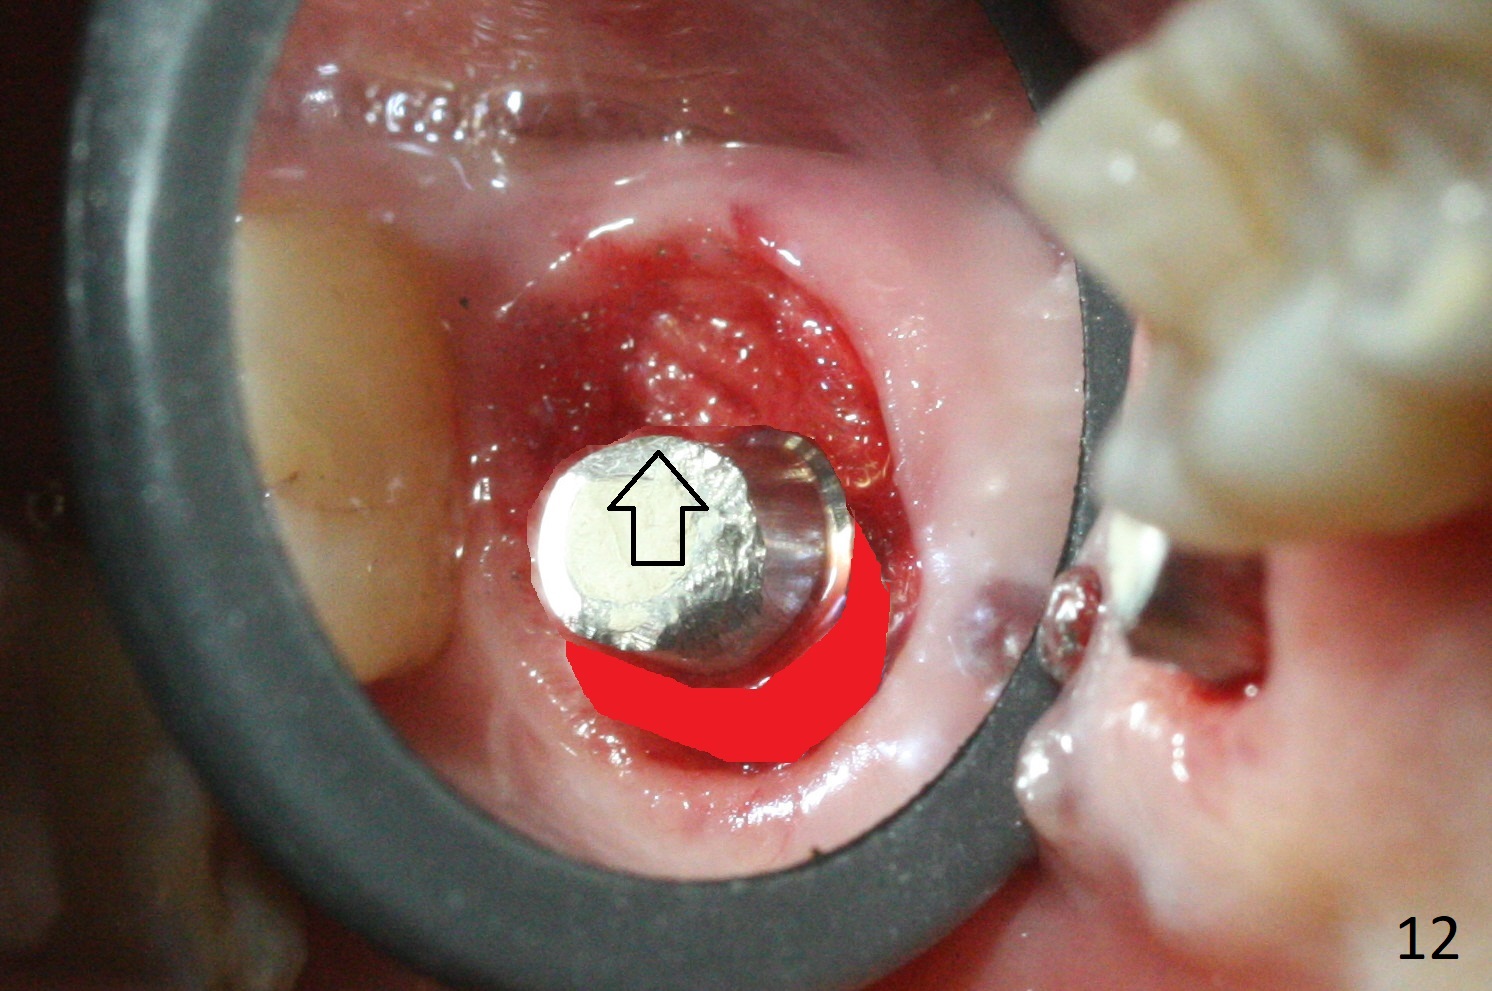

There is a fistula distal to the tooth #2 with deep pocket distopalatally (Fig.1 *), corresponding to palatal root fracture (Fig.2). There is a septum (Fig.3 S) between the buccal (B) and palatal (P) sockets. Osteotomy is initiated in the center of the septum (Fig.4 black circle). In fact the center of the socket is buccal (red circle), in which osteotomy should have been established because of the presence of the distopalatal bony defect associated with the root fracture and the distal fistula. The less ideal initial osteotomy leads to palatal placement of the implant and abutment (Fig.11 vs. 12).